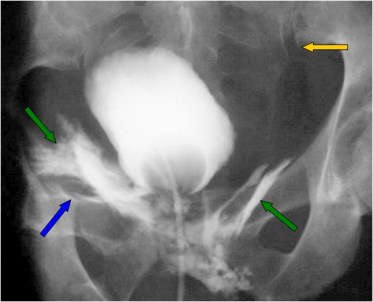

Signos de fístula colovesical en la cistografía. El extremo vesical de la fístula se asocia con la imagen de una deformidad biconvexa triangular (flechas verdes) que acaba en un punto bien definido, como si se insinuase el contraste en la boca de la fístula. De hecho puede verse contraste fuera de la vesícula, por encima de ese ángulo que forma el borde superior vesical.

En nombre del Signo de la colmena se debe a que la vejiga queda deformada adoptando una forma que recuerda a la celda de una colmena.

El Signo del heraldo es un signo temprano visible en el borde superior de la vejiga, en forma de semiluna. Es un hallazgo descrito en 1961 del que no hemos encontrado imágenes. Hemos marcado con flecha roja el borde semilunar de la vejiga, pero no sabemos si se trata en realidad de este hallazgo.

Heraldo en realidad significa “oficial o caballero que actuaba como mensajero o encargado de anunciar las noticias importantes” o “cosa que anuncia la llegada de otra”. Por ello algunos diarios han tomado este nombre, como El Heraldo de Aragón o el Herald Tribune. No vemos la relación entre este término y la deformidad de la vejiga descrita, a no ser que, al ser un signo precoz, anuncie la fístula antes de que sea visible.

También es posible que se trate de una mala traducción o una confusión entre heraldo y escudo heráldico. Por la forma de la imagen, que recuerda a un escudo o blasón, pensamos que el signo debiera llamarse, más bien, Signo del escudo heráldico.